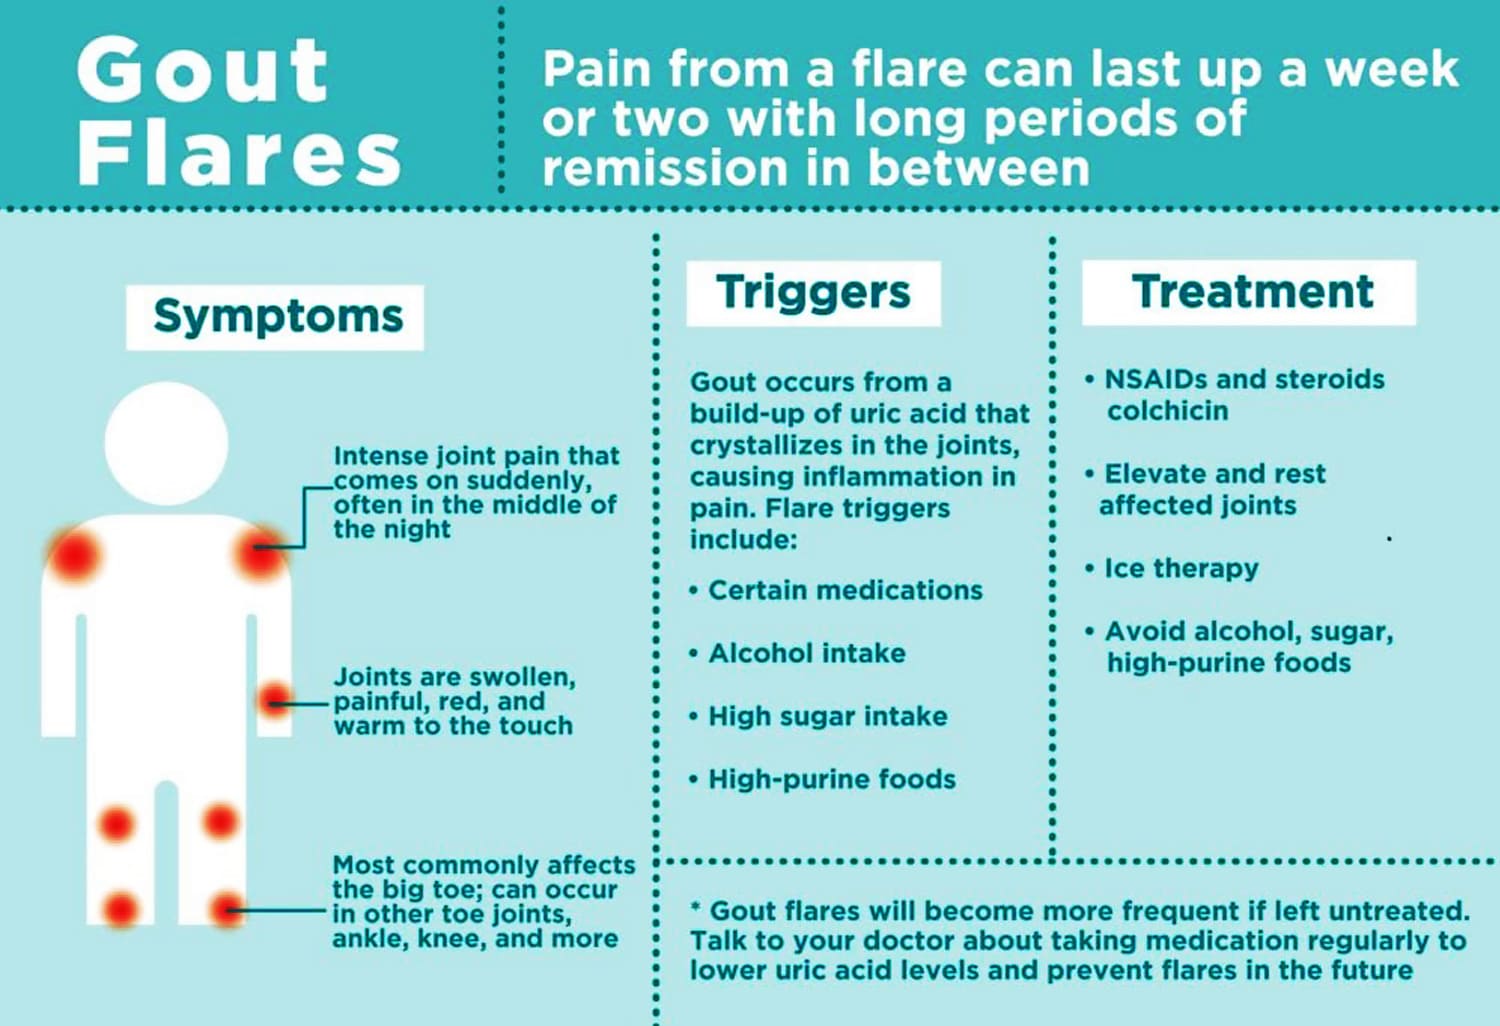

Kadar asam urat normal dalam darah berbeda antara pria dan wanita. Pada pria, kadar asam urat normal berkisar antara 3.4 hingga 7.0 mg/dL.